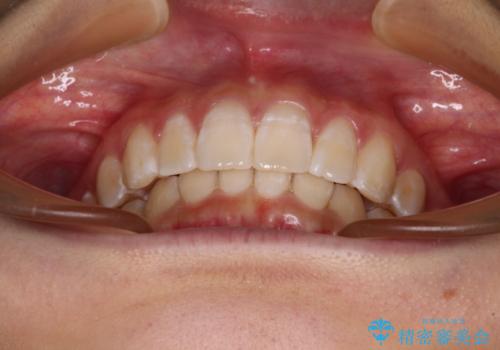

深い咬み合わせで前方に煽られた前歯 高校生のインビザライン矯正治療

- 前歯の隙間と前方に飛び出していることを気にして来院された患者様です。

奥歯の咬み合わせと深い咬み合わせを改善した後、隙間などをインビザラインで整えることとしました。

インビザラインをしっかりと装着したことはもちろん、高校生は歯の動きが早いため、非常に短期間で治療を終えることができました。